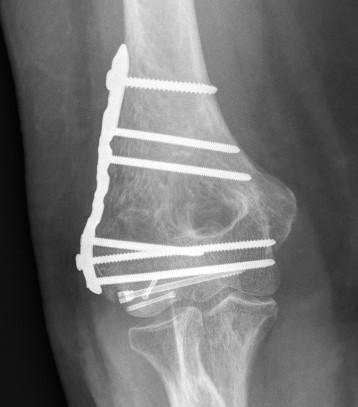

Posterolateral plate

Lateral approach and ORIF

- +/- postero-lateral plate

ORIF with PA screws and posterolateral plate

Large capitellum fracture / lateral column ORIF with plate and screws